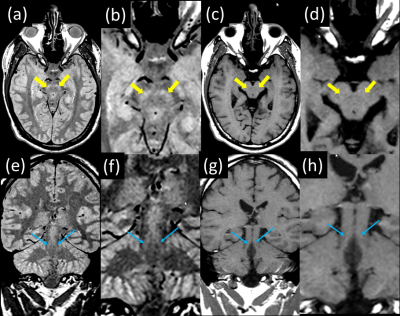

T1 mapping clearly demonstrates both elevated T1 and PD in the SN and LC compared to surrounding tissue [Fig 1]. The mean T1 value from manually drawn ROIs within the left and right substantia nigra over 2 subjects was 714 +/- 68 ms and in the locus coeruleus was 830 +/- 38 ms. This is substantially higher than the mean T1 value from ROIs in myelinated tissue neighboring the SN (572 +/- 40 ms). Thin section, PD-weighted, FSE shows clear, hyperintense signal in the SN and LC [Fig 2] whereas the T1-weighted FSE variant does not clearly visualize the SN and LC. The LC was consistently depicted in all 3 subjects and is well visualized in coronal PD-weighted FSE images [Fig 3].

Figure 2: Normal and zoomed in views of thin slice PD- plus MT-weighted FSE scans (a,b,e,f) versus T1-weighted FSE (c,d,g,h) scans. The SN (yellow arrows) and LC (blue arrows) are clearly depicted with hyperintense signal in the PD- plus MT-weighted contrast (a,b,e,f). Poor visualization of these same structures is observed in the predominantly T1-weighted scans (c,d,g,h).